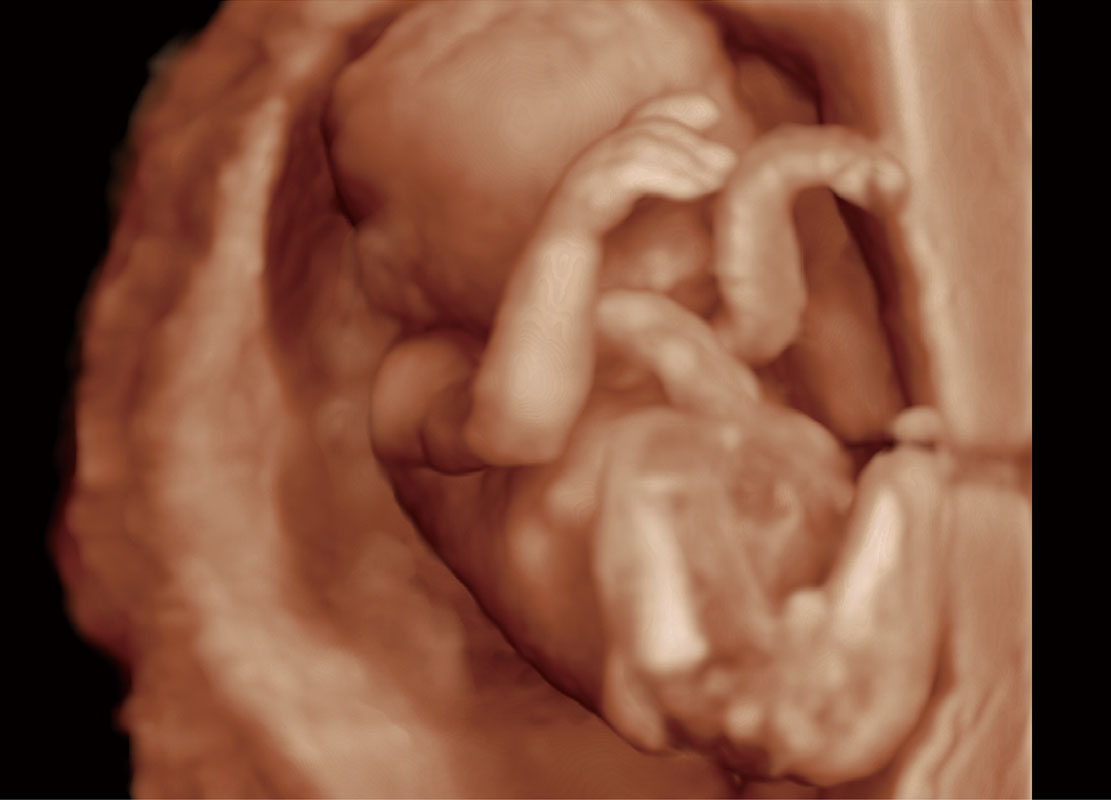

• 高分辨率容积成像-早孕胎儿